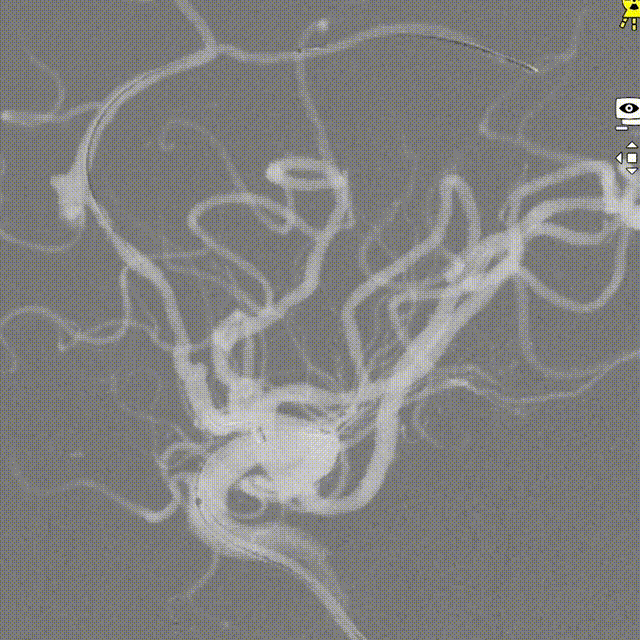

DSA:提示左侧大脑前动脉A2段动脉瘤,其他血管造影未见明显异常。

术前诊断:左侧大脑前动脉A2段动脉瘤。

治疗方案:血流导向装置植入。

微导管到位:Synchro微导丝导引支架微导管通过病变血管进入。

支架到位,远端打开(工作位):支架释放过程中,轻柔推送支架系统,支架释放,打开良好。

术后造影:支架覆盖夹层动脉瘤,贴壁良好。

术后造影:

强易达(Choydar)血流导向密网支架术中操作顺利,支架推送及释放过程平顺,未见管壁损伤,支架喇叭口形状设计贴壁效果好;径向支撑力高。